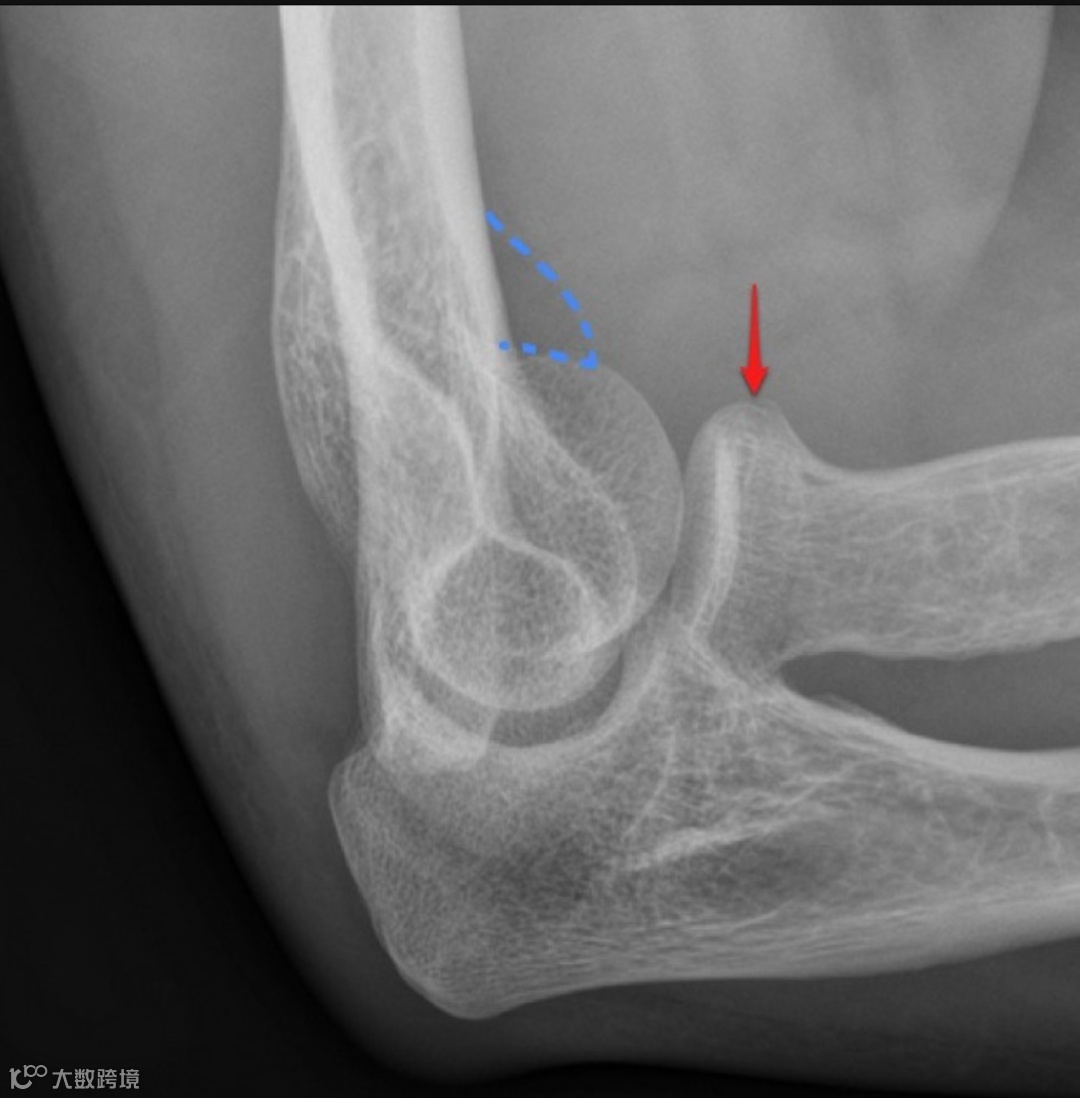

男,35岁,右肘部外伤。未见明确骨折,X线显示前脂肪垫征 [由于关节积液(黄色)将正常的肱骨前脂肪垫向上抬离其正常位置,在侧位投影上呈现三角形(蓝色)]。 关节积液较多提示可能存在骨折,最有可能的是桡骨头骨折。建议7至10天后复查X光片。